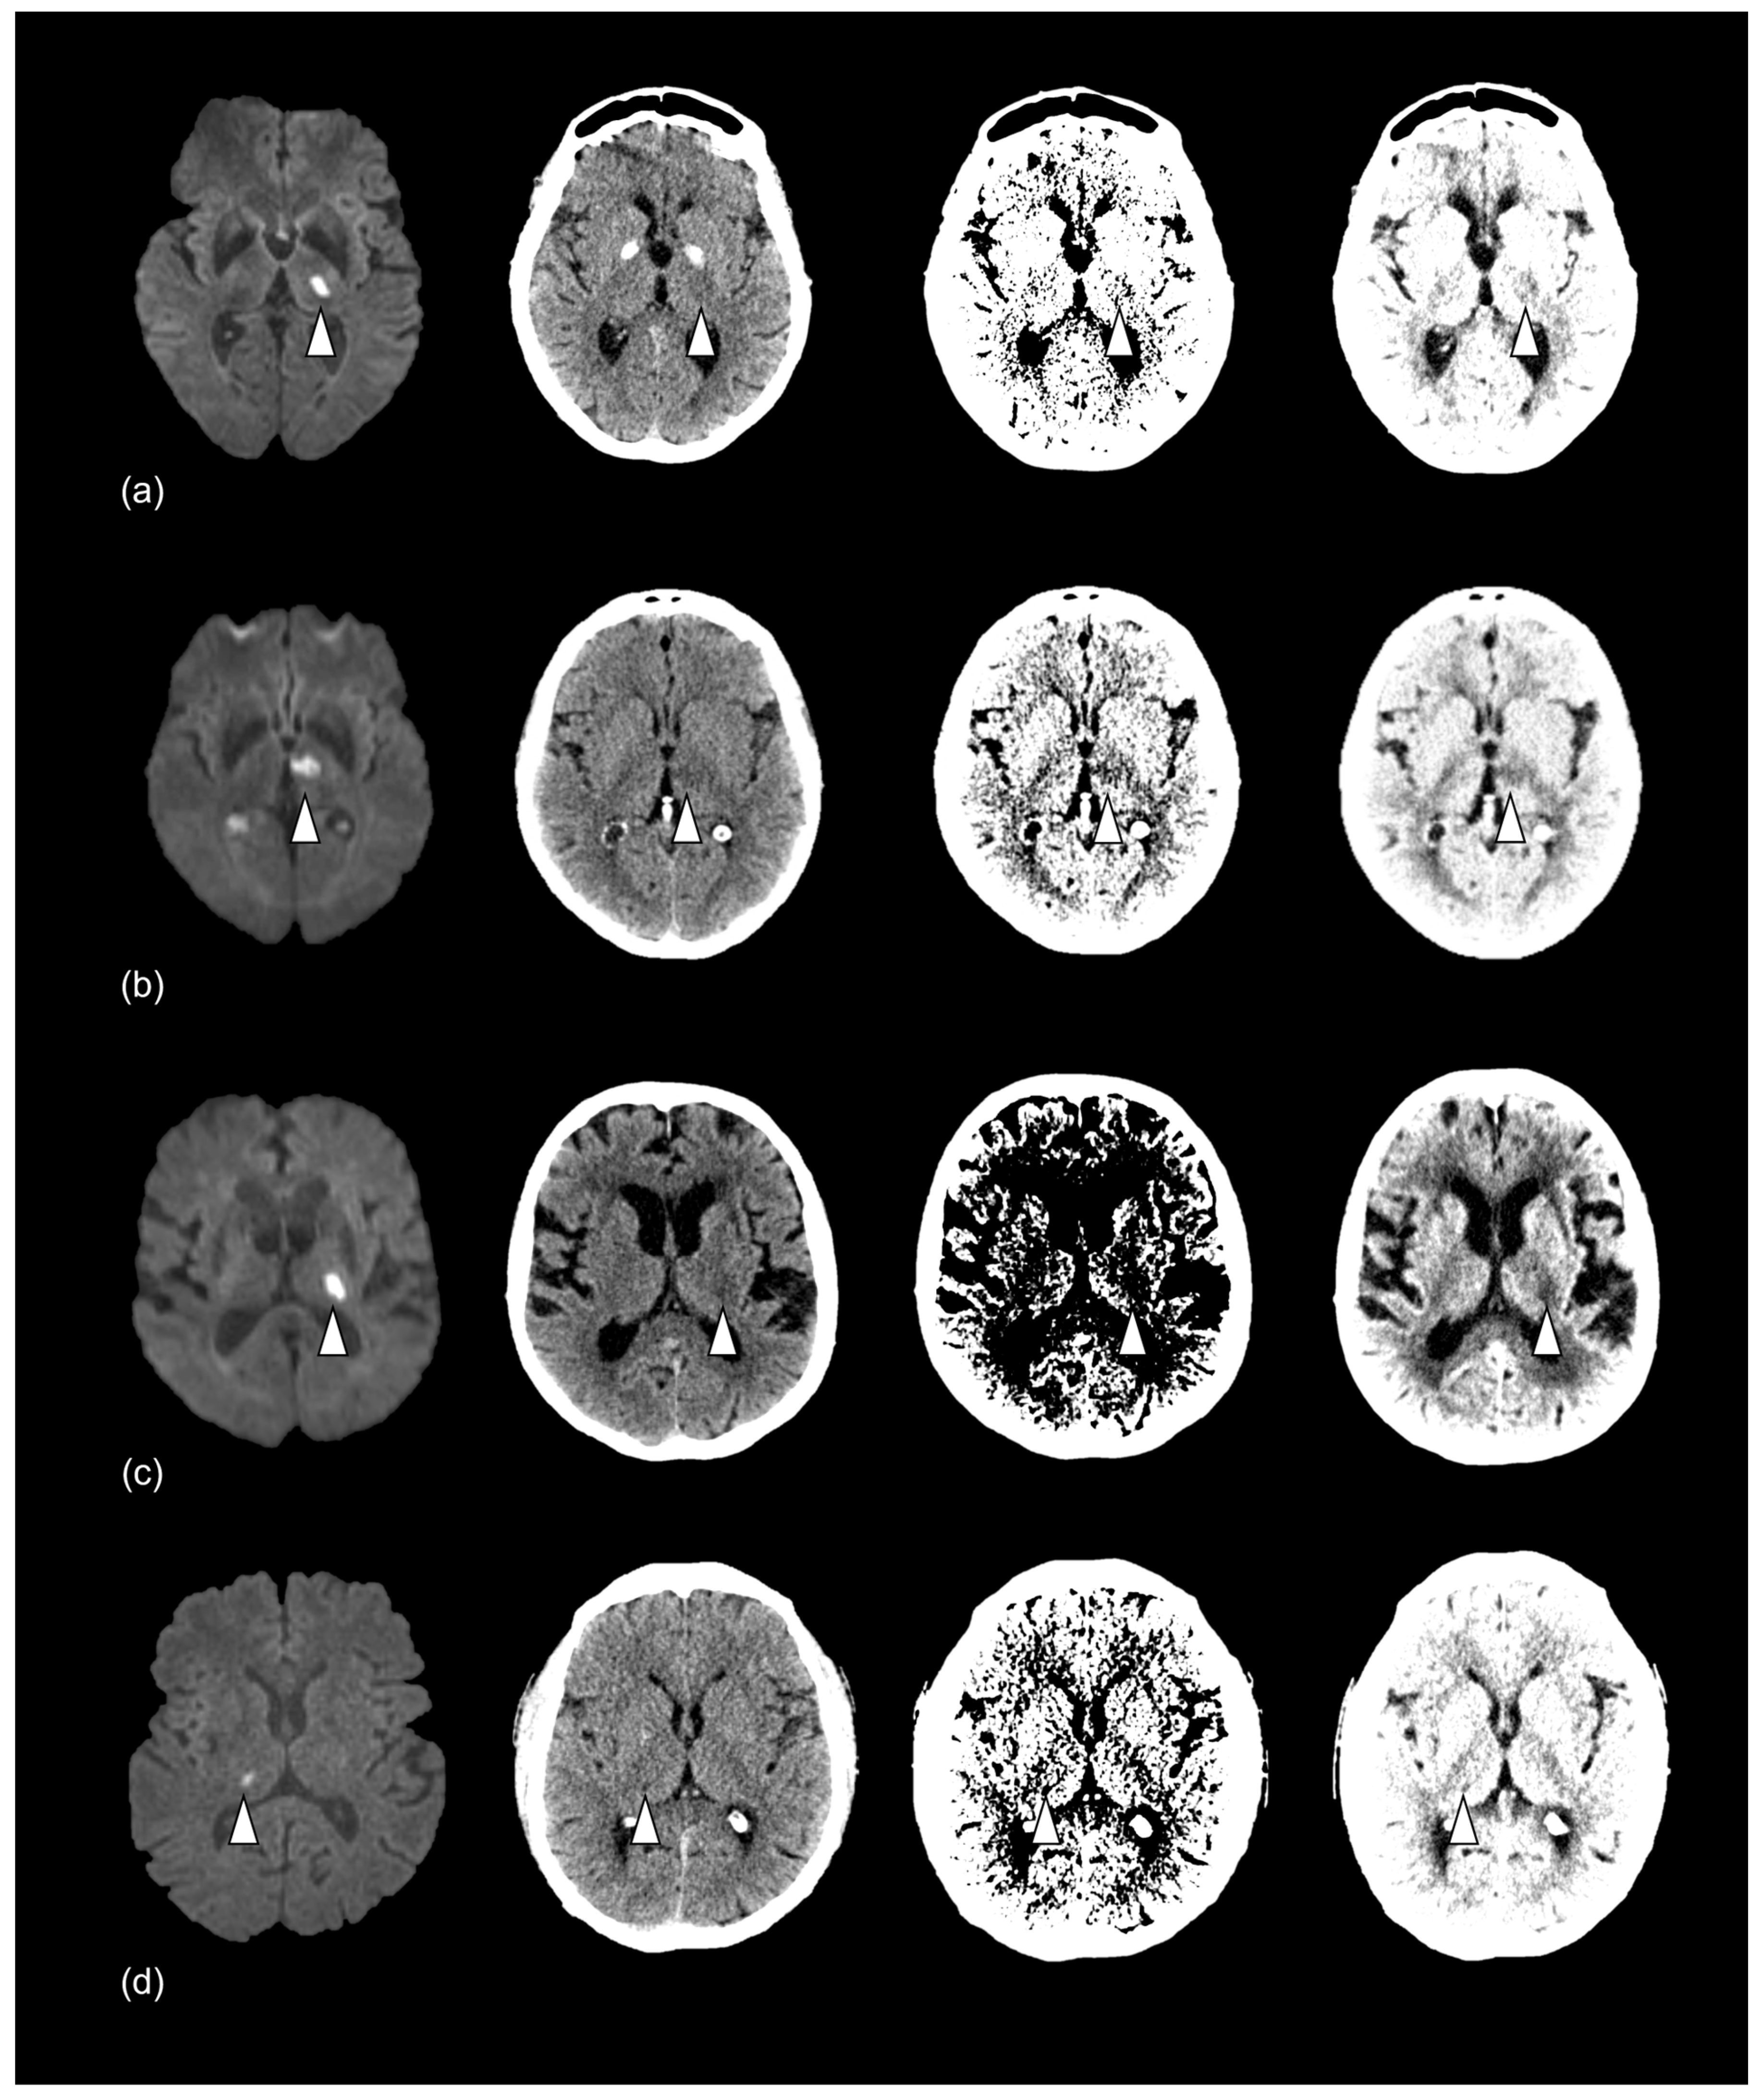

Subdividing these results into the specified time windows showed the lowest sensitivity for RSSI detection 0–6 h after symptom onset (9%). Additional infarcts were correctly diagnosed by adding the window- and BC-optimized CT 6–12 h and 12–24 h after symptom onset (Figure 3; Table 4).

Figure 3.

Imaging of thalamic RSSI for the time windows of (a) 0–6 h, (b) >6–12 h, (c) >12–24 h, and (d) >24–36 h. Confirmed infarct (white arrowhead) on DW-MRI (left) and corresponding unprocessed, window-, and BC-optimized NCCT (right), respectively. The NWU is 6.2% (a), 9.2% (b), 15.6% (c), and 24.3% (d). The infarct was not detected in any NCCT (a), detected in window- and BC-optimized NCCT (b), only detected in BC-optimized NCCT (c), and detected in all NCCT (d). RSSI = recent small subcortical infarct, DW-MRI = diffusion-weighted magnetic resonance imaging, BC = Best Contrast, NCCT = non-contrast computed tomography. NWU = net water uptake.

True positive infarct findings based on onset-to-computed-tomography-time.